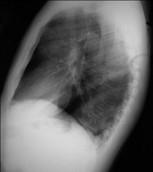

问题 47岁,男,腹泻、体重下降,伴有重症肌无力,请结合胸片和CT图,选择最可能的诊断 ( )

选项 A.胸腺增生 B.胸腺瘤 C.淋巴瘤 D.纵隔血肿 E.错构瘤

答案 B